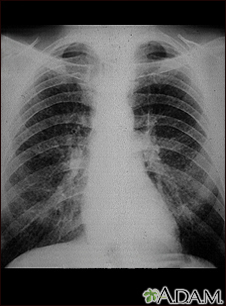

This chest x-ray shows coal worker's lungs. There are diffuse, small, light areas on both sides (1 to 3 mm) in all parts of the lungs. Diseases that may result in an x-ray like this include: simple coal workers pneumoconiosis (CWP) - stage I, simple silicosis, miliary tuberculosis, histiocytosis X (eosinophilic granuloma), and other diffuse infiltrate pulmonary diseases.